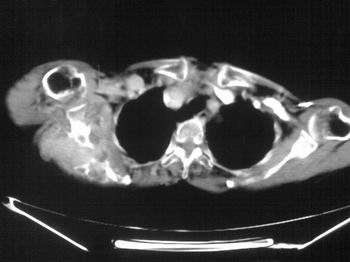

以下是引用zhangxu5888在2007-9-11 16:25:00的发言:[br]有侧肩胛骨溶骨性破坏且见软组织成分,增强软组织强化明显,中央见低密度坏死区!根据病史10年,考虑良性肿瘤恶性变!性质待定!

以下是引用老爱克斯新网客在2007-9-11 18:22:00的发言:[br]应该是良性肿瘤恶变,但因晚期破坏严重不能见到原来肿瘤征象无法判断,